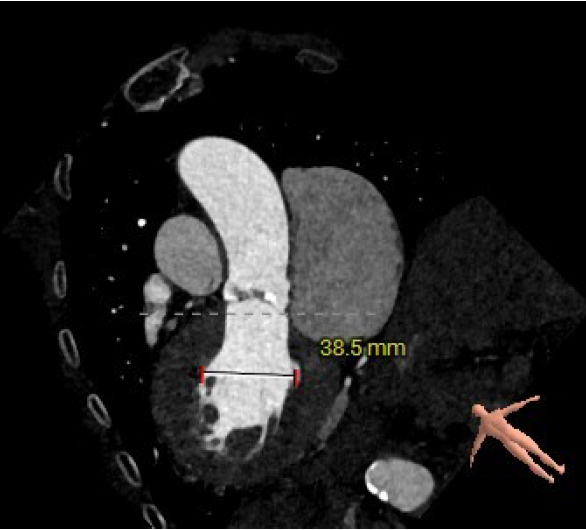

主动脉根部评估:

短轴

长轴

三叶式主动脉瓣;瓣环周长23mm,平均周长径72.1mm;左冠脉开口高度大于瓣叶长度;综合考虑冠脉风险低;LVOT周长径22.6mm;升主动脉直径32.1mm。

左冠高度12.1mm,右冠高度14.1mm;右冠脉开口高度大于瓣叶长度;SOV瓦式窦:平均周长径31.3mm;术中球囊预扩须密切注意冠脉灌注;STJ周长径26.5mm。

瓣叶重度钙化伴增厚,钙化分布不均匀

HU596 积分930mm²

左室腔内径偏小,心室壁增厚明显